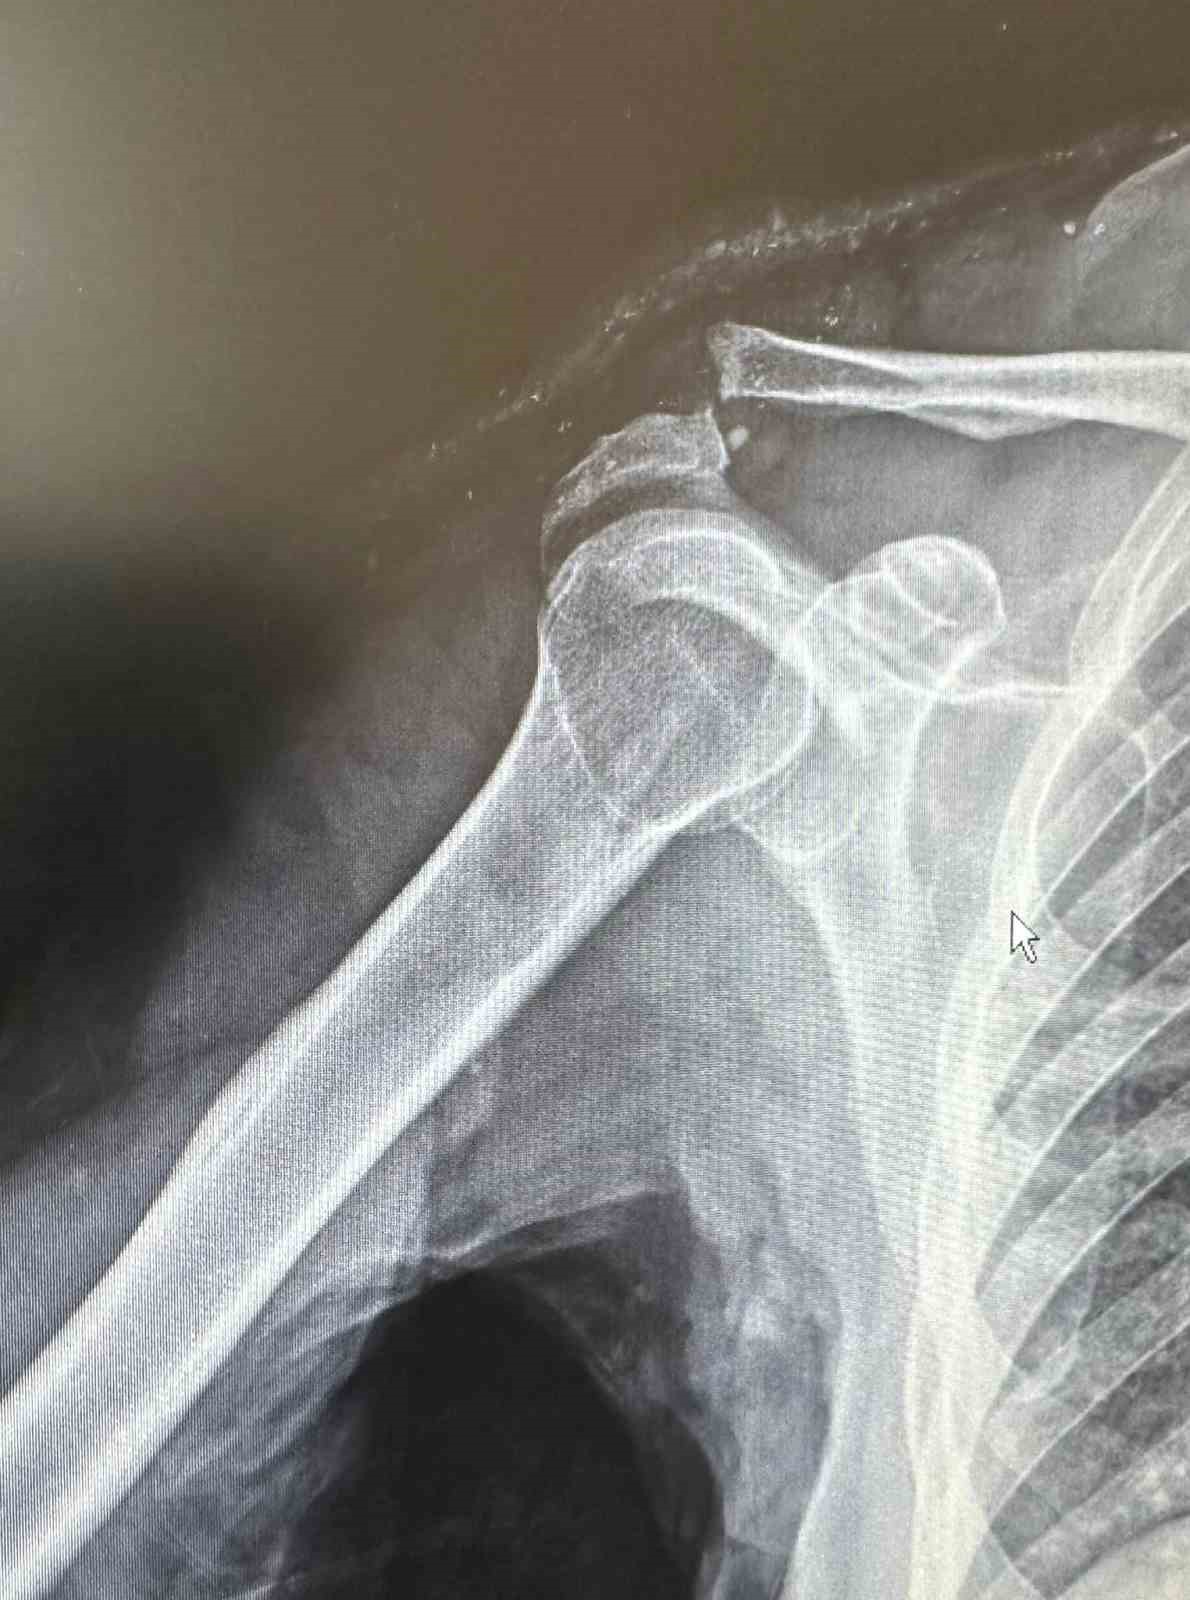

Dr. Başer, hastanın 64 yaşında omuz çıkığı nedeniyle kendilerine başvurduğunu söyledi. Kendisi, arkadaşlarıyla tenis oynarken omuz üzerine düşme sonrası omuzunda bir çıkık geliştiğini belirten Başer, "Normalde bu omuz çıkığını genç hasta grubunda görebiliyoruz. Hastamız ileri yaş olmasına rağmen aktif spor yapan bir hastamız. Bize başvurduğunda omuz eklemi yerinde değildi. Hastanın kemik yapısına tam uyumlu, nadir kullanılan özel bir plak ile başarılı bir ameliyat gerçekleştirdik. Daha sonra biz de ameliyat kararı verdik. Ameliyatında daha çok gençlerde kullanılan nadir, özel şekilli, çengel bir plak kullandık. Daha sonra filmlerini de çekip kontrol ettikten sonra hastamızın ameliyatını başarılı bir şekilde tamamladık. Başarılı ameliyatın ardından hemen fizik tedavi sürecini başlattık. Hastamız bugünden itibaren yavaş yavaş omuz hareketlerini yapabilecek hale geldi. Kol askısından bir an önce kurtulacak ve hastamız en geç 2-3 haftaya kadar eski omuz hareketlerine ağrısız kavuşmasını bekliyoruz" dedi.